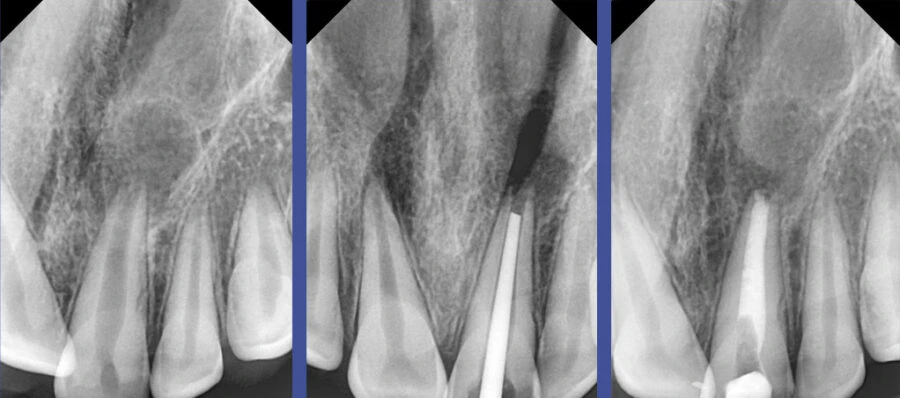

Ưu điểm của vật liệu sinh học trộn sẵn BG Multi tại Anh và Em

Sản phẩm BG Multi do ANE phân phối mang lại nhiều lợi thế lâm sàng rõ rệt. Thứ nhất là tính tiện dụng với dạng ống tiêm trộn sẵn, giúp bác sĩ tiết kiệm thời gian sửa soạn. Thứ hai là khả năng cản quang cao, giúp dễ dàng kiểm soát kết quả trên phim X-quang sau khi trám. Thứ ba, và cũng là quan trọng nhất, chính là khả năng hỗ trợ lành thương quanh chóp nhanh chóng nhờ cơ chế sinh học đặc thù. Việc sử dụng BG Multi giúp giảm thiểu đáng kể tình trạng đau sau điều trị (post-operative pain), mang lại trải nghiệm nhẹ nhàng hơn cho bệnh nhân.